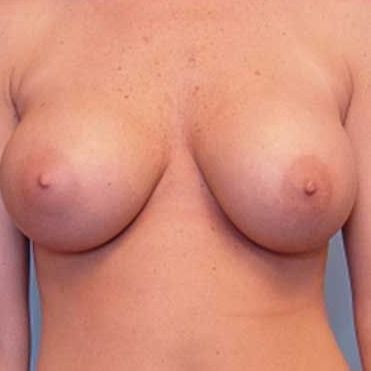

This patient presented to Dr. Agha for corrective breast augmentation. Her primary breast augmentation was performed by a non-plastic surgeon four years ago.

After the second year of her breast augmentation, she returned to her surgeon for implant drooping. According to the patient, the surgeon placed additional saline in her implants during an office procedure.

When presenting to Dr. Agha four years after her primary procedure, the patient had 450 cc saline implants in a subglandular plane, despite weighing only 90 Ibs. Her large saline implants in a subglandular plane had resulted in significant thinning of her breast tissue, skin damage, and stretching of her nipple-areola complex.

The patient underwent a corrective breast augmentation procedure that involved removing her implants, reconstructing her lower inframammary fold, placing silicone implants (275 ccs chosen by the patient) in a submuscular plane, and periareolar mastopexy to remove stretched out skin.